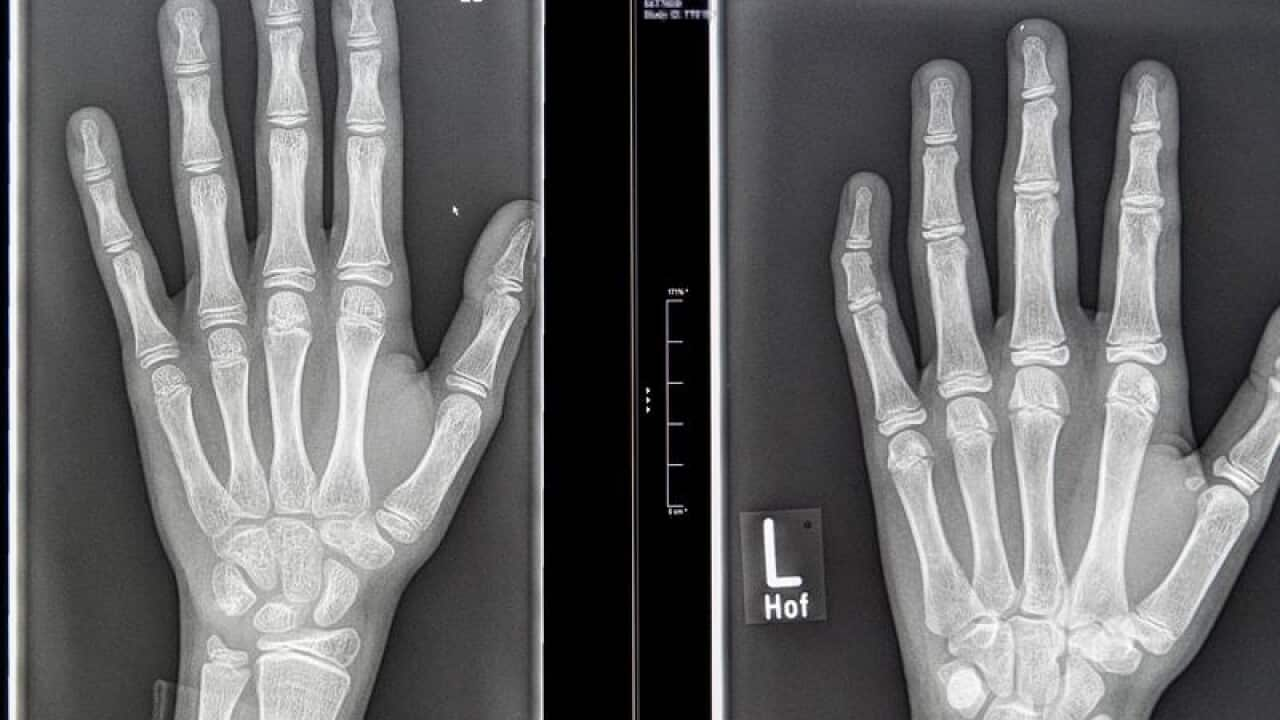

* X-rays for fractures